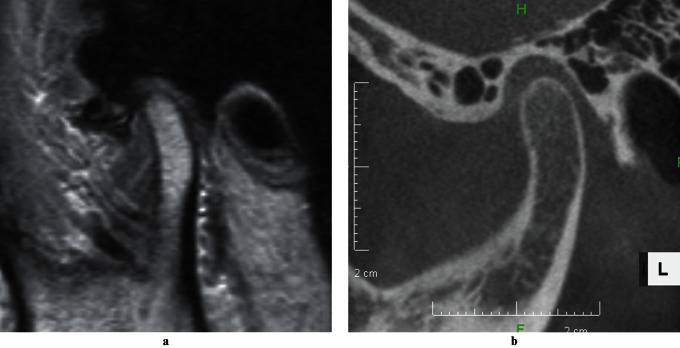

Figure 1.

MRI (a) and CT (b) images of partial disc displacement

The study included 60 joints with MRI-confirmed DD in 57 subjects aged 12–20 years (mean age 14.8 years) from a pool of post-orthodontic patients for retrospective analysis of their disc positions on LCBCT images. The MR and LCBCT images used in the study had been obtained as part of the initial examination upon informed consent, as patient history and chairside examination22 had indicated the need for objective TMJ status assessment by diagnostic imaging prior to orthodontic treatment. Subjects meeting the following inclusion criteria were enrolled based on the temporal order of the initial visit between January 2006 and September 2009: (1) no history of trauma to the face; (2) no DJD; (3) no excessive joint effusion;23 (4) no major CO–CR discrepancy at the joint level; (5) no hypertrophy of the disc; and (6) no thinning of the disc. The absence of DJD was confirmed on open-mouth MR images according to the severity and non-reducing status of DD, and joints with marked osseous alterations on CBCT images were excluded.24 T2 weighted MR images were used to detect excessive joint effusion. CO–CR discrepancies at the joint level were checked with a condylar position indicator (CPI; Panadent, Grand Terrace, CA) to exclude vertical and anteroposterior discrepancies of 1.8 mm or more and transverse discrepancies of 0.6 mm or more.25 Overt hypertrophy or thinning of the disc was identified with MRI. The subjects who met these criteria were divided into four DD groups: partial DD (PDD), total DD with reduction (TDDWR), lateral DD (LDD) and medial DD (MDD). PDD was defined as a posterior band of the disc displaced to the middle third of the eminence on one or two of the three sagittal (medial, central and lateral) MR slices examined (Figure 1a). TDDWR was defined as a more advanced stage of DD where one or two of the three sagittal slices revealed the displacement of a posterior band down to the inferior one-third of the eminence, the remaining sagittal slice(s) not showing a posterior band within the superior one-third of the eminence (Figure 2a). Figure 3 is a schematic representation of normal disc position, PDD and TDDWR in the sagittal plane. A medial or lateral component of DD had to be less than one-quarter of the disc width in the coronal plane for both PDD and TDDWR. LDD was defined as one-third to one-half of the disc displaced laterally on the coronal MR slice, but the posterior band was retained within the superior half of the eminence on the lateral sagittal slice (Figures 1 and 4). Figure 5b illustrates LDD, as defined in this study, compared with the normal disc position in the coronal plane (Figure 5a). MDD was defined as one-third to one-half of the disc displaced medially (Figure 5c) on the coronal MR slice.